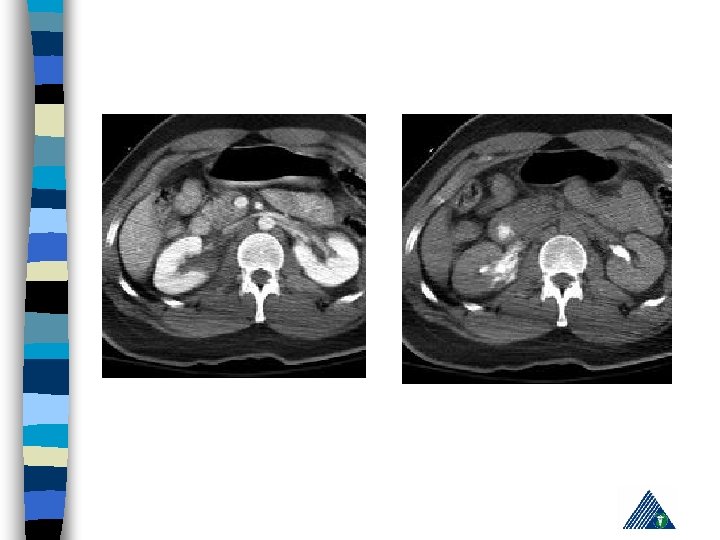

Renal Trauma n Blunt : (85 -90% ) – vehicle accident, fall, rapid deceleration, iatrogenic n Penetrating : Gunshot and (85 -90 % associated with intraabdominal or thoracic injury)

Renal Trauma - Diagnosis History n PE (lumbar echimosis, pain with palpation) n Hematuria n – (Renal vascular injury - 36 % not associated with hematuria) n Variable clinical presentation (asymptomaticshock)

Radiologic Imaging n n n KUB (loss of psoas or renal contour) IVU (delayed renal function, nonhomogenous collecting system) USG (lumbar hematoma and urinoma lokalizasyonu) Computerized Tomography Renal angiography

American Association for the Surgery of Trauma Organ Injury Severity Scale for the Kidney Grade Tip Tanım 1 kontüzyon Mikroskobik ya da gross hematuri, ürolojik incelemeler normal hematom Sub. Kapsuler, genişlemeyen parankimal hasar yok hematom Genişlemeyen perirenal hematom , renal retroperitona sınırlı laserasyon <1 -cm derinlikte parenkimal korteks hasarı, üriner ekstravazasyon yok 3 laserasyon >1 -cm derinlikte parenkimal korteks hasarı, üriner ekstravazasyon yok 4 laserasyon Medulla ve toplayıcı sisteme ulaşan parenkim hasarı vasküler Renal arter ve vende hemoraji içeren hasar laserasyon Tamamen parçalanmış Böbrek vasküler Renal hilusun ayrılması 2 5

Expectant Management: n Hemodynamically stable, well defined and non-expanding injury on CT scan n 88 % patienst are observed n If there is associated gross hematuria, admit and observe